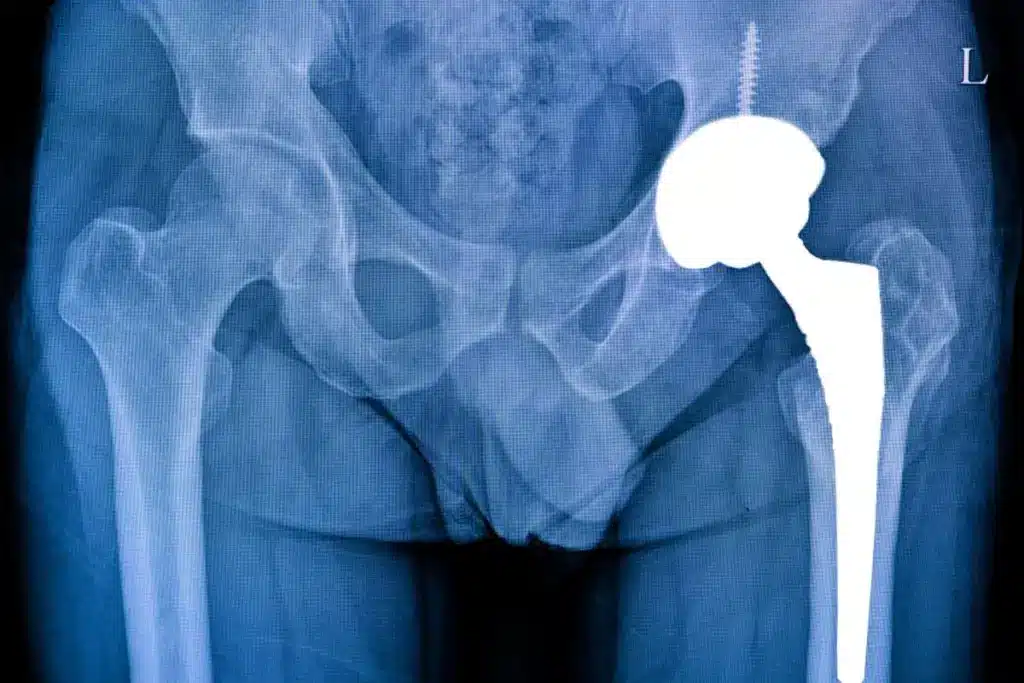

Understanding Hip Replacement Surgery

It’s important for patients to understand hip replacement surgery. This surgery, also known as hip arthroplasty, is for hip pain and stiffness. It’s often due to arthritis or fractures.

Types of Hip Replacement Procedures

There are many types of hip replacement surgeries. Each one is chosen based on the patient’s needs. The most common is total hip replacement. This involves replacing both the acetabulum and the femoral head with prosthetics.

What Happens During Hip Replacement Surgery

During hip replacement surgery, a surgeon replaces the damaged hip with a prosthetic. This is done to ease pain and improve movement for those with severe hip issues.

- The old hip is removed and replaced with a new one.